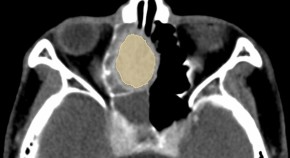

A goal of cancer research is to develop specific and sensitive tumor-imaging techniques for early detection while minimizing background signals from nontarget, 'normal' tissues. The authors have designed a 'pH-activatable' probe, consisting of a targeted macromolecule (monoclonal antibody) and a fluorescence probe, which is activated after internalization in the lysosomes of targeted cancer cells. The utility of this approach for imaging HER2-positive lung cancer cells in mice is shown.